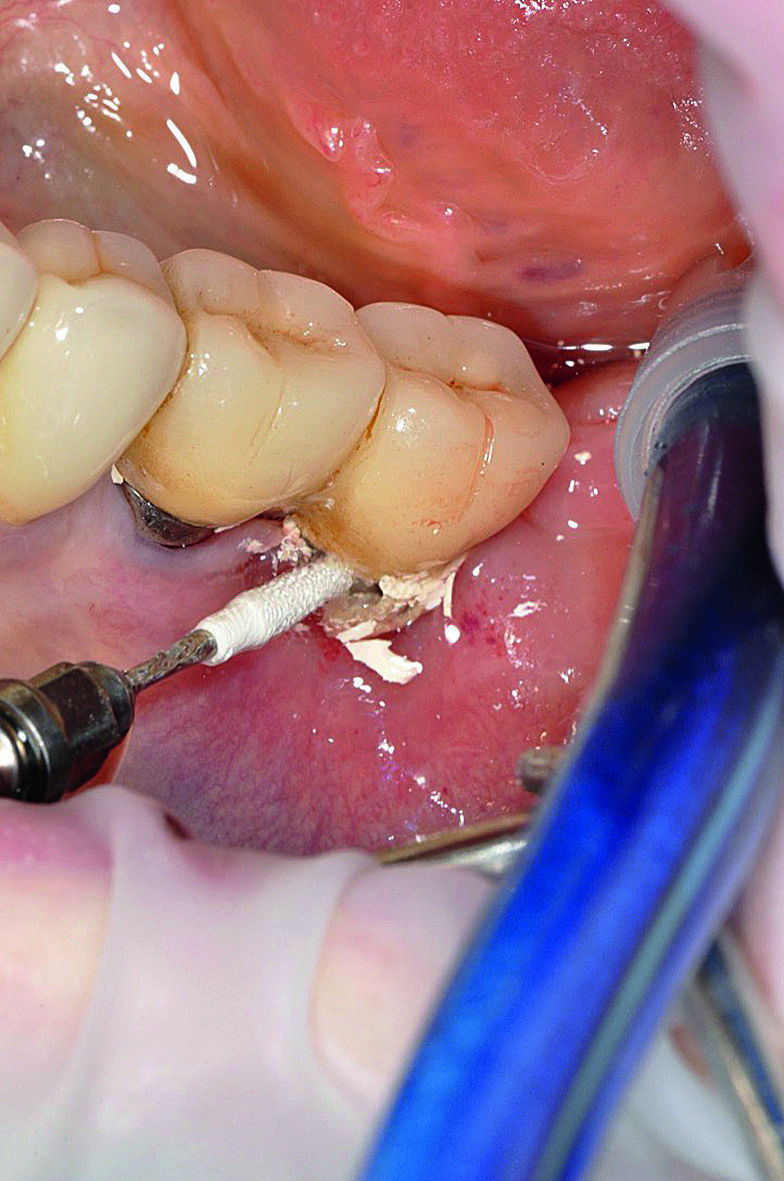

Fig. 3 : Excès de ciment autour de l‘implant

Le prothésiste dentaire doit travailler en contact direct avec le chirurgien-dentiste afin de créer des espaces permettant un nettoyage confortable et esthétiquement plaisants, adaptés au patient. Après avoir reçu les instructions et les informations de l’hygiéniste bucco-dentaire, les patients doivent être en mesure de nettoyer leurs prothèses quotidiennement et presque sans effort afin de maintenir leur santé orale.13 Un autre facteur important associé aux signes cliniques de péri-implantite est l’excès de ciment.14–17 Pour éviter cet excès, les limites marginales de la restauration doivent être situées au niveau ou au-dessus du bord péri-implantaire de la muqueuse ; sinon l’excès de ciment doit être éliminé.18 En dépit de la littérature internationale démontrant l’intérêt accru que suscite l’excès de ciment considéré comme l’un des facteurs clés dans l’étiopathogénie de la péri-implantite, un protocole standard guidant le clinicien dans cette délicate procédure d’élimination doit encore être mis en place. Selon l’auteur, la technique de scellement demande du temps, de l’attention, le port de loupes binoculaires et de la minutie. C’est pourquoi un protocole précis, dépendant de la composition du ciment, doit être publié (Figs. 7 et 8).